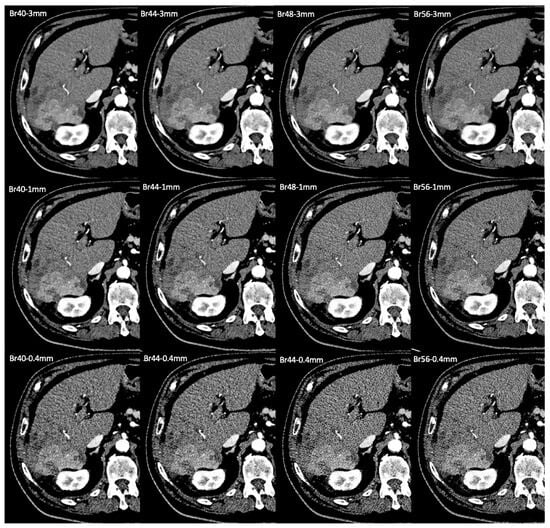

2.3. Image Reconstruction

For each patient, the same raw data taken from the arterial phase were reconstructed in 12 data sets of images using four different sharpness kernels (Br40, Br44, Br48, and Br56) and three different slice thicknesses of 0.4 mm, 1 mm, and 3 mm. A polyenergetic dataset was acquired at 120 kVp to ensure high-quality, low-noise data with excellent tissue penetration. Level 3 quantum iterative reconstruction was used for image reconstruction. Images were reconstructed at 60 kilo-electronvolts to optimize contrast and enhance diagnostic utility for abdominal imaging. The median pixel size was 0.7 mm (0.62 mm–0.88 mm) with a variable field of view from 317 mm to 451 mm (median 358 mm) and a fixed matrix of 512 × 512. An average volume of 77 ± 8 mL of contrast agent was injected at an average flow rate of 3.5 ± 0.5 mL/s. Acquisition and reconstruction details are also displayed in Table 1.

In our study, the standard kernel and slice thickness was, overall, a good mix for the assessment of HCC and other upper abdominal structures, with only minor improvement with Br44 and Br48 in single instances. The improvement of vascular imaging at 1 mm slice thickness with kernels Br44 or Br48 warrants further research to determine whether this type of reconstruction should be separately performed, especially if interventional procedures, such as transarterial chemoembolization, are to be planned. However, the submillimeter slice thickness of 0.4 mm and the very sharp kernels of Br56 did not bring any significant advantage for vessel assessment. An example of all of the reconstruction sets is given in Figure 5. Similar to what was described by Milos et al. [16] for thoracic imaging, using a submillimeter slice thickness (0.4 mm) did not result in any additional value for the visualization of other abdominal structures or liver pathology. Instead, this only led to worse image quality. On the other hand, Mergen et al. have demonstrated a decreased vessel sharpness and more blooming artifacts, but better CNR, SNR, and lower image noise when using 0.6 mm slice thickness compared with 0.2 mm for ultra-high-resolution cardiac imaging [14]. Similarly, lower kernel sharpness resulted in decreased vessel sharpness and more blooming artifacts. However, this study was performed in the ultra-high-resolution mode that was not available in our patients.

Figure 5. Examples of photon-counting CT in the arterial phase in a patient with liver cirrhosis and a hepatocelluar carcinoma (HCC) in the right posterolateral sector. Each subimage represents a certain reconstruction setting, which is depicted in the left upper corner of the image. Br403 mm, which served as the reference standard, was compared with each set. One mm reconstructions were rated higher for vascular assessment (best for kernels Br 44 and Br 48) and slightly better for overall image quality in the Br40 kernel. Although noise was lowest in the standard setting, readers felt the increased sharpness of higher kernels and thinner slices was beneficial for the assessment of smaller vessels and structures with a clear edge, like the renal cortex.